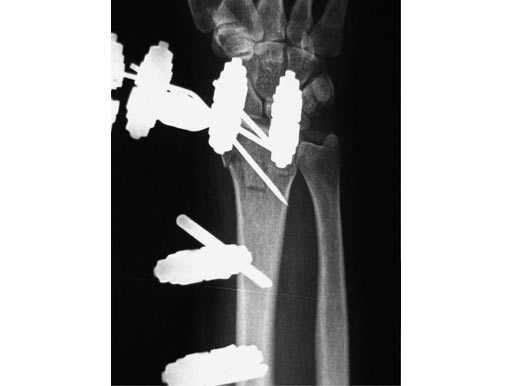

Nonspanning Distal Radius Fixator

Treatment of fractures of the distal radius has been proven to be advantageous if spanning of the wrist joint is avoided. This allows for greater motion throughout the treatment resulting in improved range of motion, grip strength, and dexterity. The nonspanning Distal Radius Fixator provides such a nonbridging external fixator, creating a low-profile frame for increased patient comfort and the ability to perform daily activities.

The nonspanning Distal Radius Fixator consists of a small adjustable clamp, nonspanning, MR safe. It locks on to two 4.0 mm Schanz Screws spaced 20 mm apart. The 4.0 mm carbon fiber rod slides into a through hole in the clamp with a set screw tightening point to established the desired length. A ball joint in the clamp then provides for ulnar/radial as well as volar/dorsal deviation of the rod. To create lower profile frames, the nonspanning Distal Radius Fixator includes three shorter length Schanz screws65 mm lengths in both 4.0/2.5 mm size (with a trocar tip) and the 4.0/3.0 mm size (with a self-drilling tip), and an 80 mm length in the 4.0/2.5 mm size (with a trocar tip).

The 4.0 mm curved carbon fiber rods match the axial curvature of the wrist. They are available in 60, 90, 120, or 180 arcs to be used for fixation of the distal fragment.

The 4.0 mm angled T-bar carbon fiber rods create the same angle as the curved rods, with the addition of a rod extending perpendicularly. The material allows a frame to be constructed with a rod centred on the dorsal aspect of the wrist without sacrificing the C-arm image in the dorsal/palmar view. The angled T-bar fiber rods will be available in 80 mm (length) 50 mm (width), 80 120 mm, 110 50 mm, and 110 120 mm. Both the curved and angled T-bar fiber rods can be used as part of a delta frame construct.

56-year-old female, accident at home